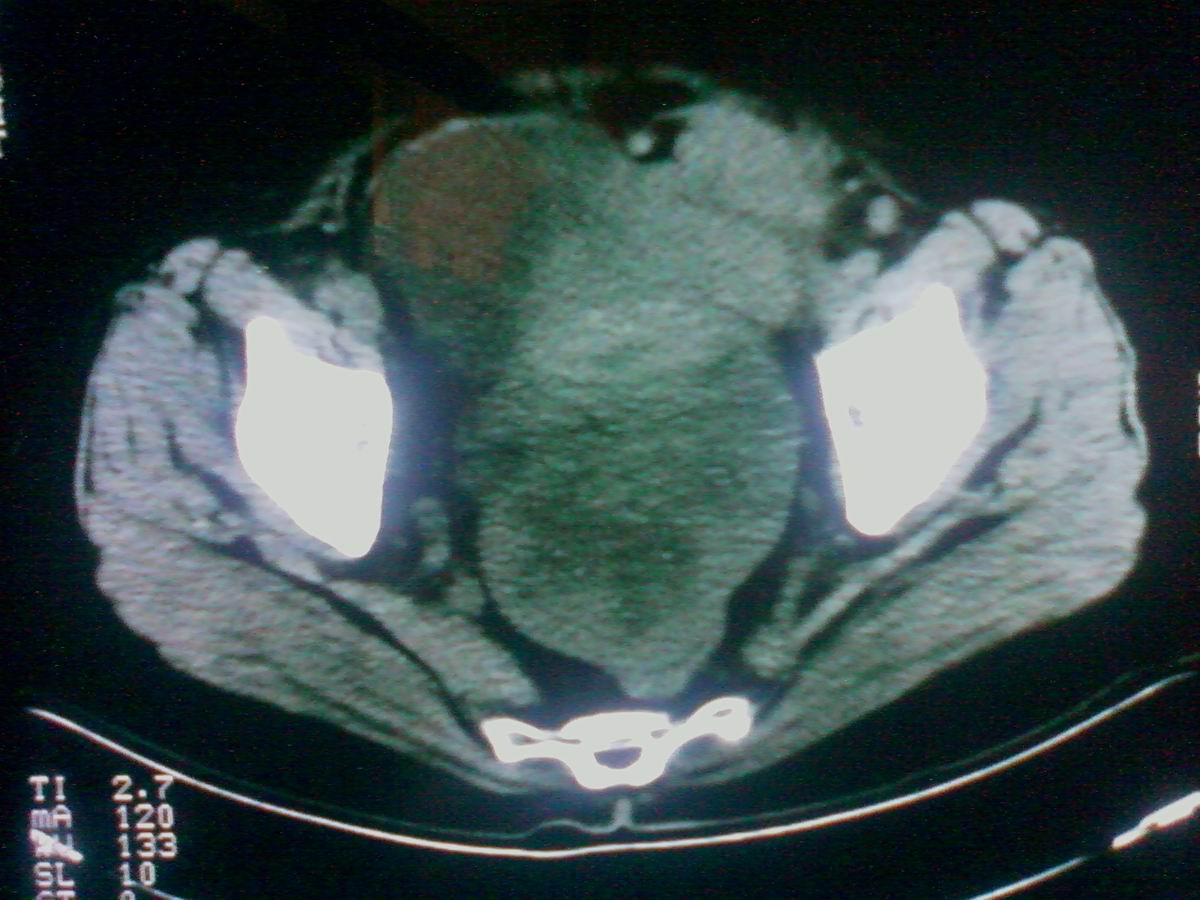

标题: CT25799:女性患者,45岁,腹胀,上腹部疼痛来诊,B超示盆腔 [打印本页]

标题: CT25799:女性患者,45岁,腹胀,上腹部疼痛来诊,B超示盆腔

考虑卵巢癌伴腹水

1)考虑卵巢恶性肿瘤。2)腹水。